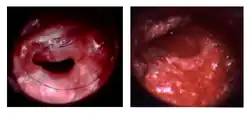

Before and after a tympanoplasty | |